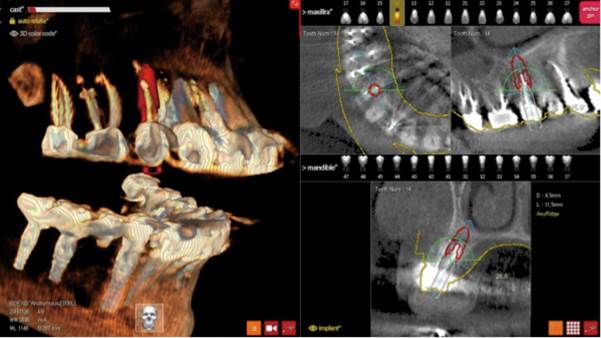

Clinical case: Digital Data Save concept in upper jaw premolar area

- Courtesy of Dr. Lysov Alexander Dmitrievich & Dr. Sofronov Matvey Vitalievich, Russia -

Keywords

AnyRidge, R2GATE, R2GATE guide, ISQ value, initial stability, immediate loading, KnifeThread, maxillary posterior, #14, Digital, Dr. Lysov Alexander Dmitrievich, Dr. Sofronov Matvey Vitalievich, zirconia abutment, CAD/CAM crown

“AnyRidge & R2GATE show stable results

after immediate extraction, immediate implant placement, & immediate loading,

even with low bone density.”